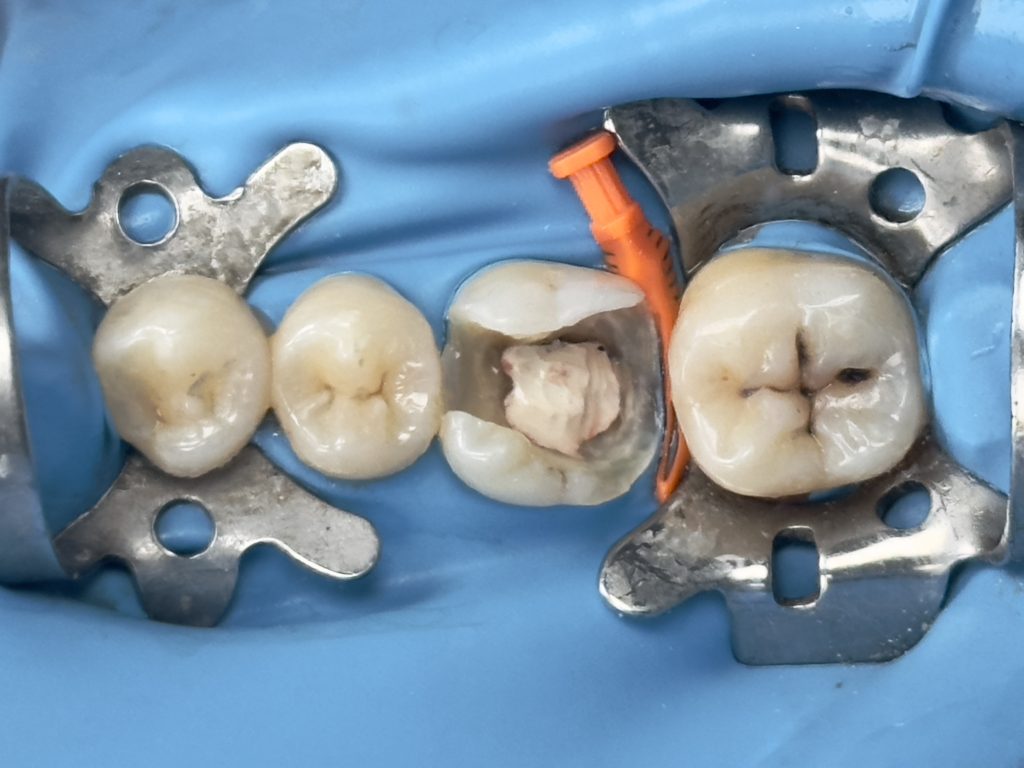

Patient (dentist) came complaining from amalgam restoration placed 3 years ago and caused multiple tooth fractures

1st visit :-

-Complete amalgam removal

-gingival trimming of the inflamed gingival caused by over hanging margin

-clean & neat margin

-IDS & RC

-DME (matrix sealed with teflon &diamond wedge)

-ever X posterior to increase fracture resistance